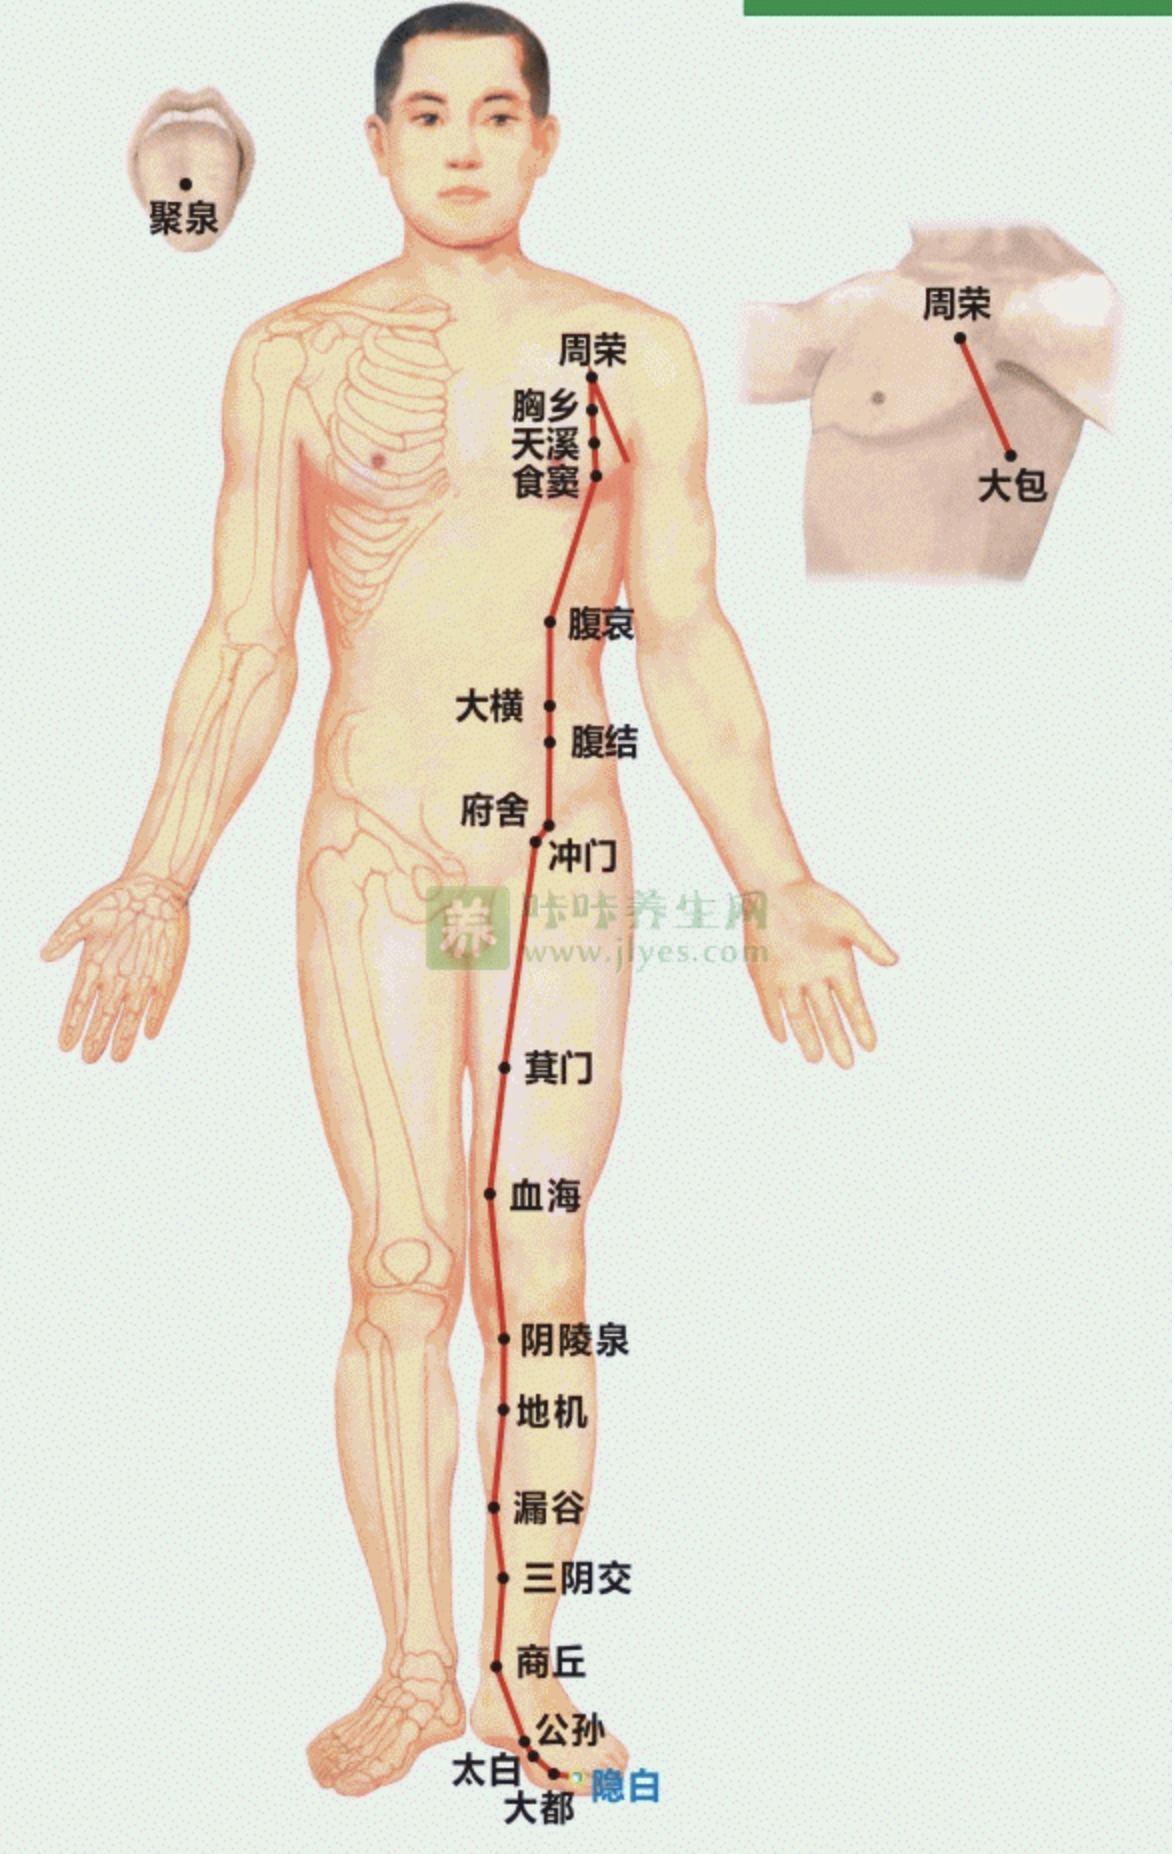

【(四)足太阴脾经(图10-22-1)】

1、时辰 巳时 9 ~ 11

2、歌诀 足太阴脾由足拇,隐白先从内侧起,大都太白继公孙,商丘直上三阴交,漏谷地机阴陵泉,血海箕(jī)门冲门前,府舍腹结大横上,腹哀食窦(dòu)天溪连,胸乡周荣大包尽,二十一穴太阴全。

3、经脉循行 起于足大趾末端(隐白),沿着大趾内侧赤白肉际,经第一跖(zhí)趾关节向上行至内踝前,上行腿肚,交出足厥阴经的前面,经膝股部内侧前缘,进入腹部,属脾络胃,过膈上行,夹咽旁系舌根,散舌下。

胃部支脉:过膈流注于心中,与心经相接。

从大趾末端开始(隐白穴),沿大趾内侧赤白肉际(大都穴),经核骨(第一骨小头后(太白穴、公孙穴),上向内踝前边(商丘穴),上小腿内侧,沿胫骨后(三阴交穴、漏谷穴),交出足厥阴肝经之前(地机穴、阴陵泉穴),上膝股内侧前边(血海穴、箕门穴),进入腹部(冲门穴、府舍穴、腹结穴、大横穴;中极穴、关元穴,属于脾,络于胃(腹哀穴;会下脘穴、日月穴、期门穴),通过膈肌,夹食管旁(食窦穴、天溪穴、胸乡穴、周荣穴;络大包;会中府穴),连舌根,散布舌下。

它的支脉:从胃部分出,上过隔肌,流注心中,接手少阴心经。

4、主要病候 胃脘痛、食则呕,嗳气,腹胀便溏,黄疸,身重无力,舌跟强痛,下肢内侧肿胀,厥冷。

5、主治概要 主治脾胃病,妇科,前阴病及经脉循行部位的其他病证。